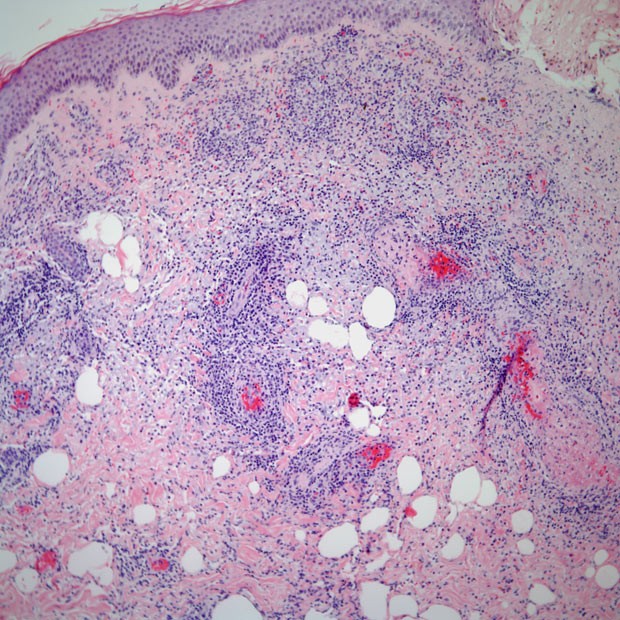

图说 ▍非霍奇金淋巴瘤(下篇)